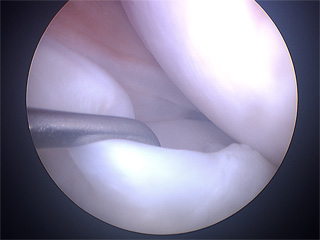

Arthroscopy is a common surgical procedure which lets orthopaedic surgeons to see inside the knee joint. It is done under spinal anesthesia and through small incisions around your knee, so that the joint does not have to be opened up fully. The surgeon will make two small cuts (less than 6 mm.) on both sides next to the patellar tendon. A tiny camera will be inserted into your knee through one of the cuts. The camera is attached to a video monitor, thus the image is sent to the monitor and surgeon can see the structures of the knee joint in great detail as the surgical technique procedure.

Knee arthroscopic procedures should begin with an exploration to make a diagnosis. Doctor should examine carefully every joint in a systemic way, in order to bring to light undiagnosed injuries by imaging test.